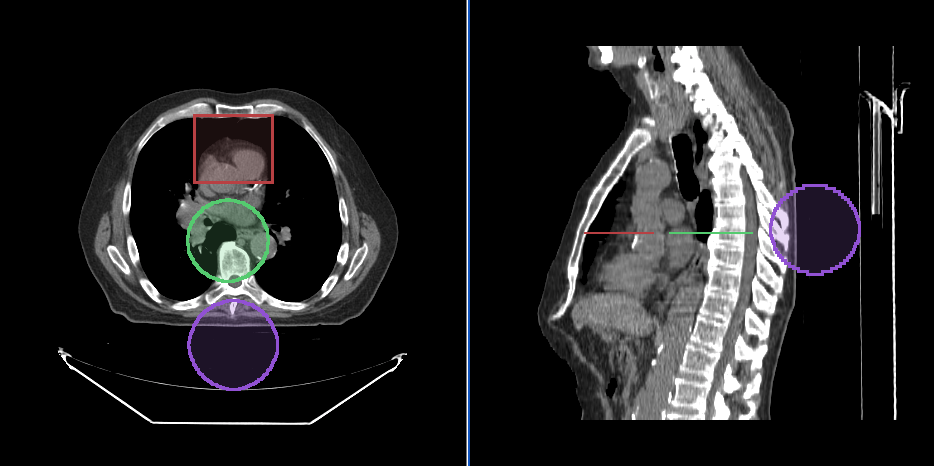

Below, you can see a screenshot of the annotation tools that are available in Cornerstone3DTools.

Segmentation Tools

Cornerstone3D also provides segmentation tools. This includes 3D SegmentationDisplay and 3D segmentation editing tools such as brush, rectangle and circle scissors, and 3d sphere tools.